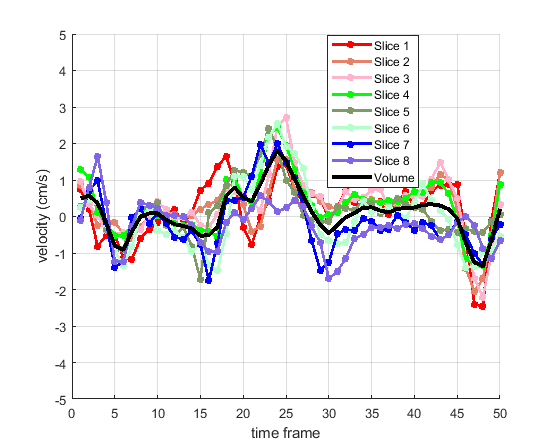

Time courses of the estimated translational component per subject, frame, slice and volume along the 3 velocity directions x, y and z are presented in Fig.6 - Fig.8.